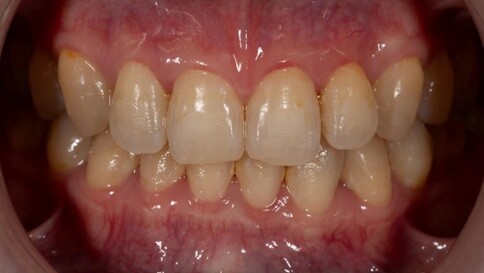

✨ 二、 兩顆的正中對決:對稱美學

Case 6:僅用兩顆全瓷冠解決色差與中軸偏差。